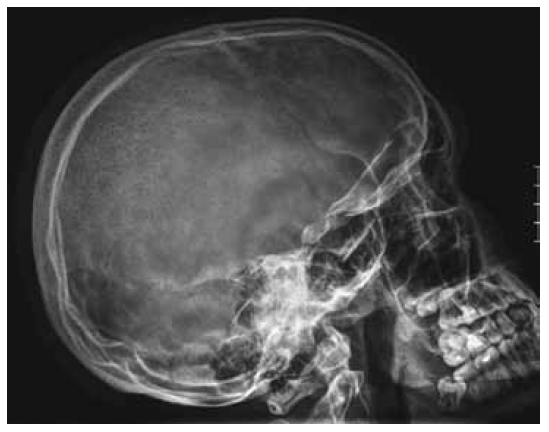

Lateral skull radiograph showed areas of osteolytic changes along the frontal and temporal bones, and osteolytic like area covering the most of the lambdoid sutures (Fig. 4).

Fig. 4. Lateral skull radiograph showed areas of osteolytic changes along the frontal and temporal bones, and osteolytic like area covering the most of the lambdoid sutures